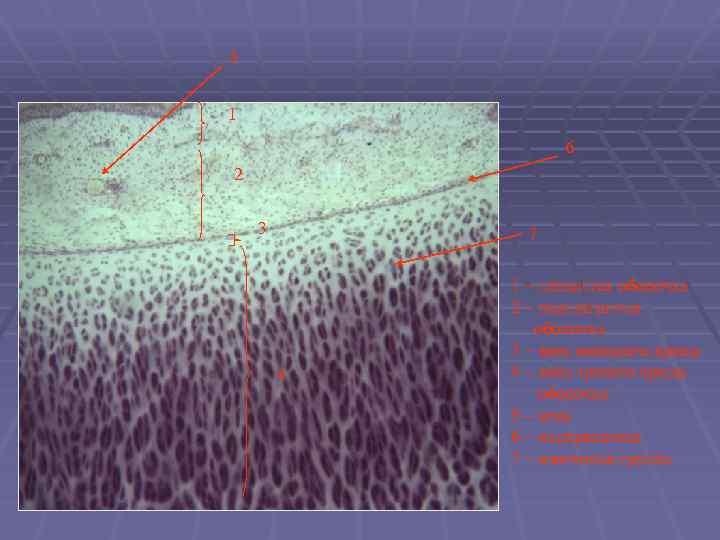

7 6 1 5 2 3 4 1 – слизистая оболочка 2 – подслизистая оболочка 3 – фиброзно хрящевая оболочка 4 – адвентициальная оболочка 5 – концевой отдел железы 6 – выводной проток 7 – бокаловидная клетка

5 1 6 2 3 7 4 1 – слизистая оболочка 2 – подслизистая оболочка 3 – зона молодого хряща 4 – зона зрелого хряща оболочка 5 – вена 6 – надхрящница 7 – изогенная группа